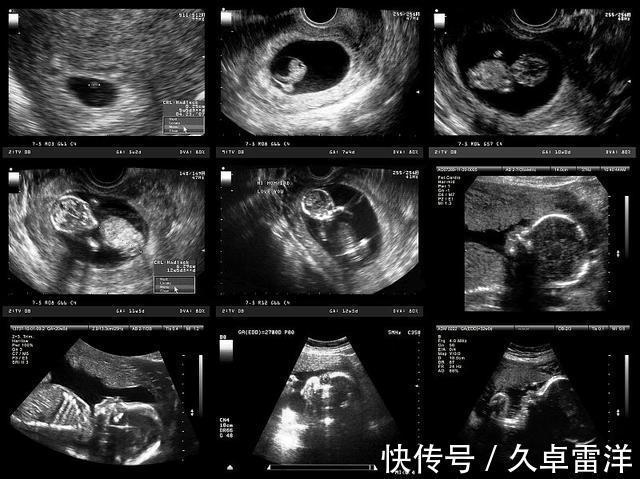

孩子|每次产检结果正常,孩子生出后发现畸形,医院需要负责吗( 二 )

3、畸形儿的诱因很复杂其实畸形儿问题一直都是育儿领域的难点,无数知名研究机构围绕着它研究了几十年,解决了不少难题,但其中依旧存在很多无法解释的谜团。比如畸形儿到底是从哪一个环节开始出错的,是孕早期还是孕中期,亦或是精卵结合时就已经注定如此?再比如病状细胞到底是什么诱发的?毕竟唯有知道问题的源头,我们才能对症下药,做好预防。曾有专家感叹过,如果谁能把畸形儿问题研究透彻了,人类基因问题将会被解决80?整个科学界都无法解决的难题,医院当然没什么办法做到100?准预测。